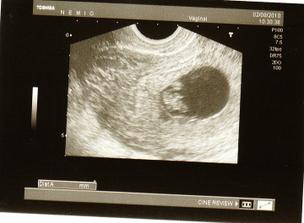

2.8. Něco mi říkalo, že se něco děje, tak jsem navštívila doktora. Na UTZ byl vidět slabý hematom, dostala jsem na týden Ascorutin a na další kontolu mám přijít za čtrnáct dní, tj. 16.8. Srdíčko ale tluče jako zvon a hematom vypadal, že se rozpouští. Bude to v pořádku🙂 Máme 11,6mm.